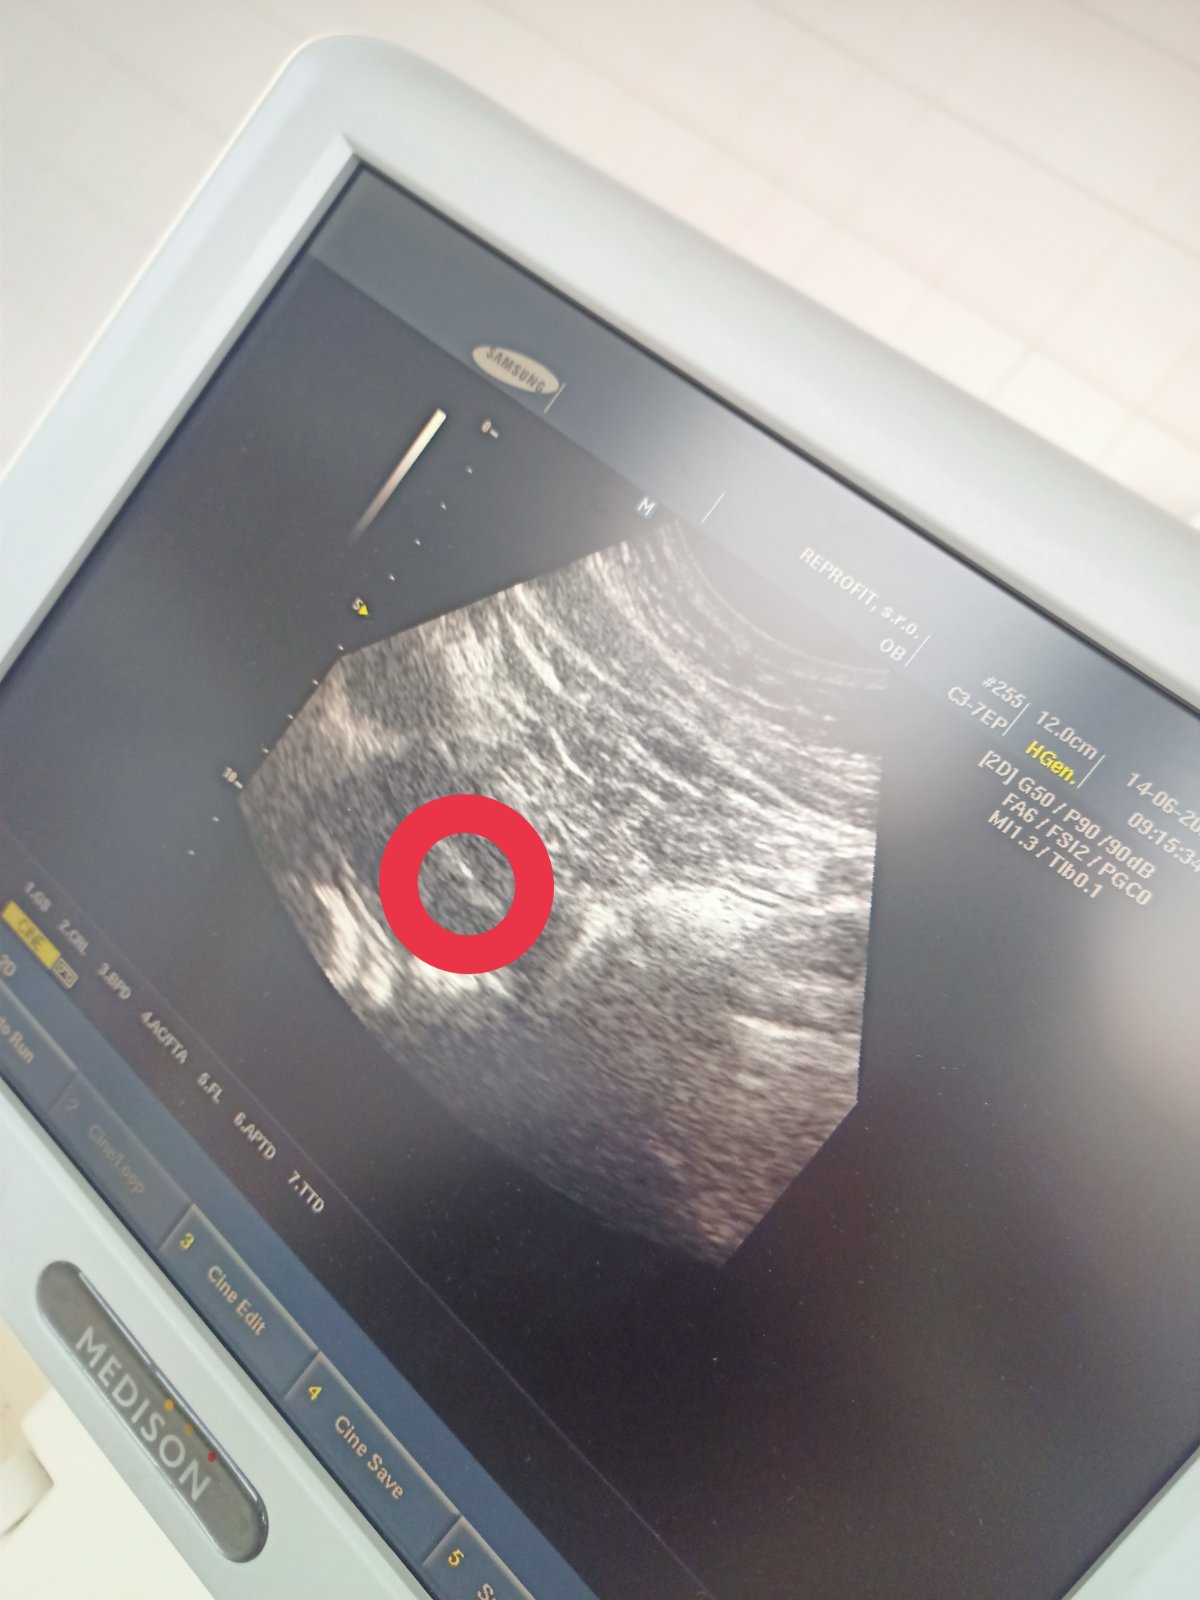

Já se na utz moc těším až tu svoji bublinku uvidím, snad už bude mít i srdíčko zlaticko moje.

První UTZ to bude nádhera 🤗 pamatuji si první se synem...ach